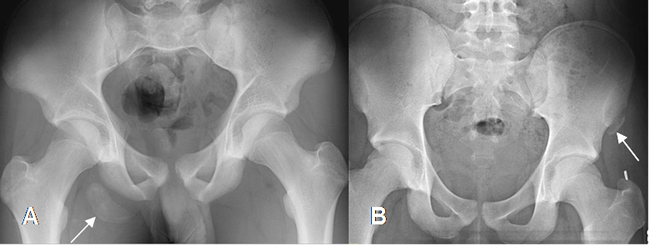

Con la Rx simple se puede detectar una avulsión, que puede estar desplazada o no. (Fig 27 y 28). (7).

Fig 27. Avulsión.

A: Rx AP. Avulsión de la tuberosidad isquiática derecha.

B: Rx AP. Avulsión de la espina iliaca anterior superior izquierda.